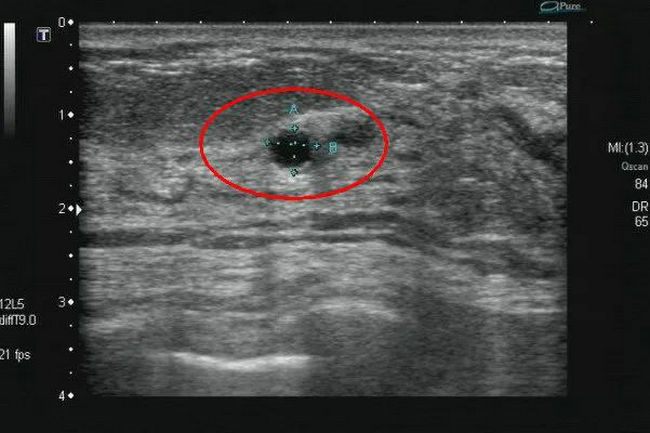

▲ 乳腺囊肿

超声报告单中,对于各类结节都会有详细描述,其中椭圆形或圆形、边界清晰、未见血流信号的以良性居多。而纵向生长、形态不规则、边缘不清楚、内有点状及簇状钙化、血流信号丰富的,则要警惕恶性病变的可能。